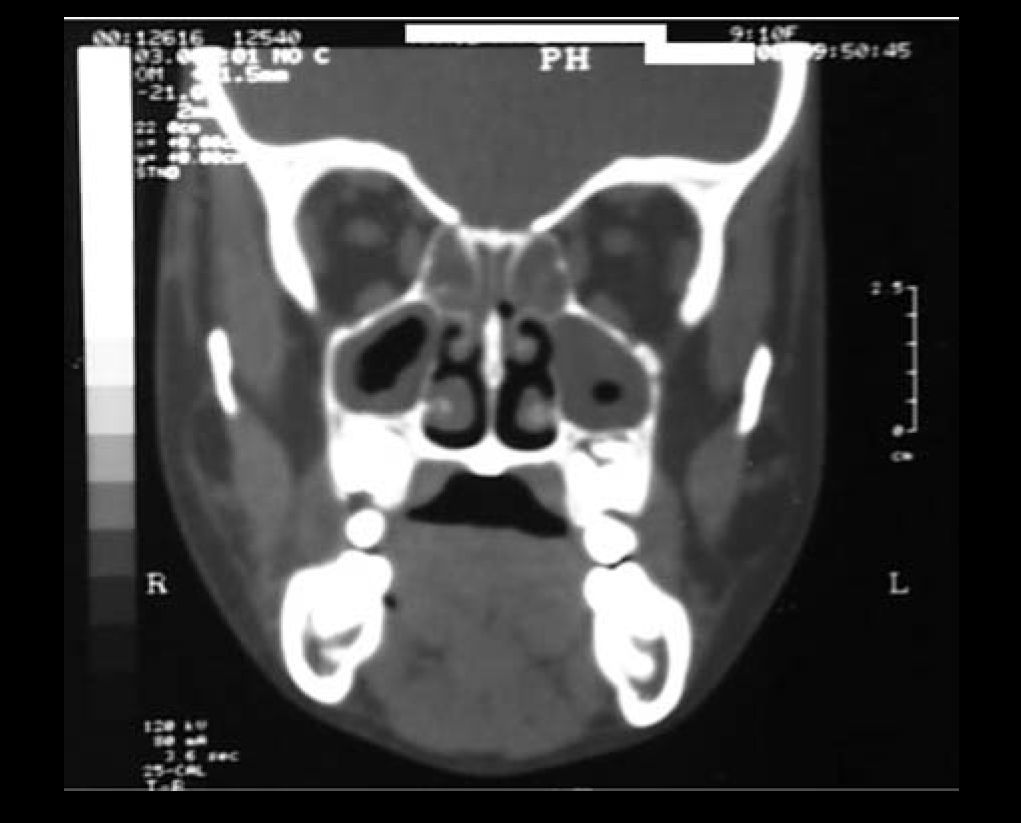

After two days, patient evolved to worsening of symptoms with significant headache. Then, CT scan of the facial sinuses was requested (Figures 1 and 2). Ceftriaxone therapy was maintained and patient was reevaluated the next day. A new CT scan was requested and right-sided eyelid edema was detected and patient still had the same complaints. Another CT scan was requested and the images confirmed the existence of periorbitary abscess. Drainage was performed on the same day with incision of the superior medial right orbit and dissection extended to the abscess with a counter incision of the nasal fossa through the ethmoid and placement of a Pen Rose drain. Next, nasal cavity was cleaned to remove any lumps and residues of fibrin, bleeding was almost negligible despite massive lower turbine necrosis (highly bleeding region) suggesting Behçet-related vasculitis.

Patient evolved properly until the second postoperative day with mild improvement of clinical symptoms. In the 3rd day, however, she had and exacerbation of eyelid edema followed by fever (39º Celsius). CT scan of paranasal sinuses was then requested, and the report reinforced the idea that a more comprehensive resection was required. Biopsy of the mucosa of the right maxillary sinus showed: “Necrotic tissue in granulation tissue areas with chronic and unspecific inflammation and massive fibrin deposition”.

Martins et al.10 published in an unheard-of fashion a likely association between Behçet's Syndrome and rhinosinusopathy in a male patient (47 years old) that also developed chronic bilateral middle ear otitis and CT scan findings were similar to those of the patient of this study (predominantly maxilla-ethmoidal with destructive characteristics). They concluded, however, due to the inexistence of a reliable histological marker, that clear documentation of such association should be postponed.